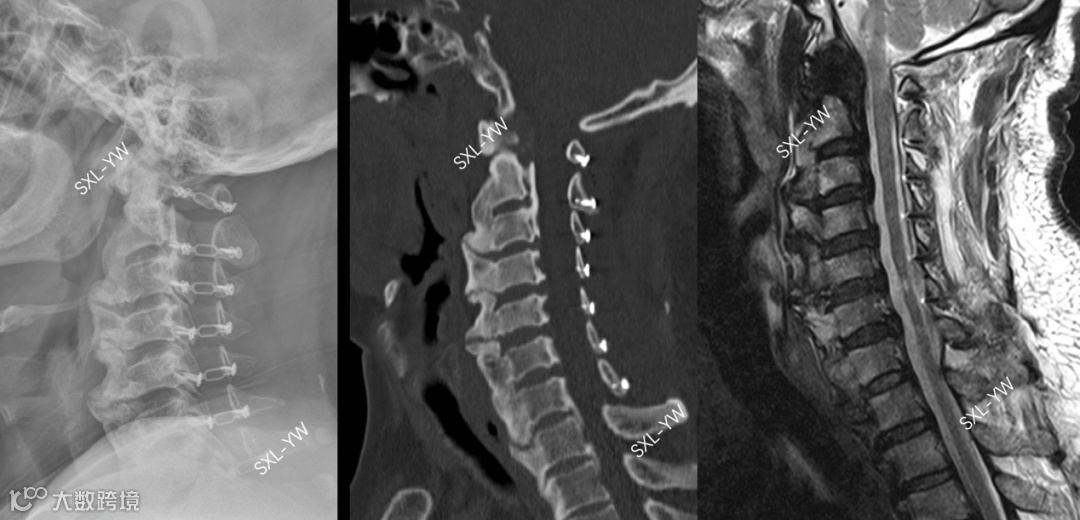

②K线对OPLL累及上颈椎、上胸椎不适用,骨化位置不定、手术节段不定,但评价指标的测量位置却是固定的,这显然是不合理的,如果手术节段超过C2-7的范围,还能用K线来评价吗?如果OPLL累及上颈椎或上胸椎,且需要手术处理,此时不能用K线来评价。

我们认为,K线阴性单开门术后脊髓漂移不充分的根本原因在于:手术节段不足,延长手术节段会明显改善脊髓漂移程度及走行状态[7]。K线采用C2-7固定的标准来预测单开门手术价值,严重限制、束缚了单开门手术的使用;再加上一些文献报道C2、C7有多个重要肌肉韧带的附着、不要手术破坏,这样又将单开门手术范围缩小到C3-6。

上述观点主观地缩小了单开门手术的适应范围、限制了单开门手术的推广,是典型的作茧自缚。PCS评分是来源于脊髓后方的评价指标,在手术方式的选择、手术节段的确定等方面,起到了至关重要的作用,我们认为PCS评分能扫除K线对单开门手术的禁锢、能扩大单开门手术的适应证、为单开门手术的推广应用做出贡献。